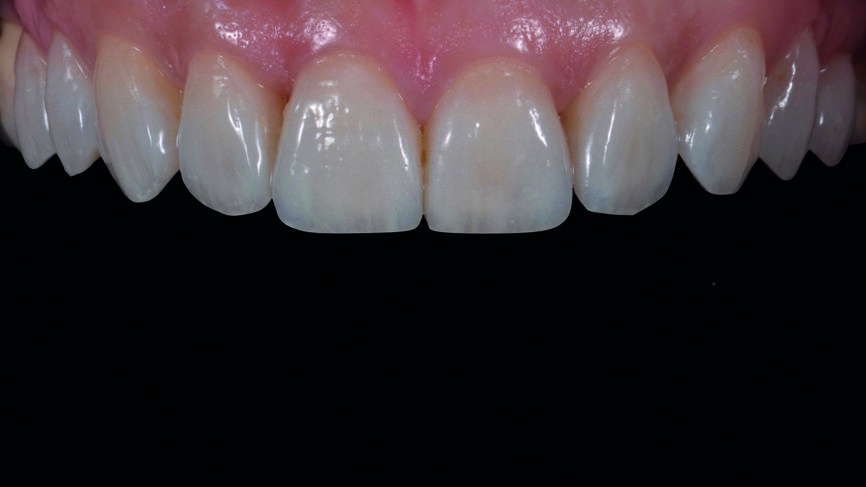

Une patiente âgée de 35 ans s‘est présentée au cabinet dentaire avec le souhait profond d‘un changement de l‘esthétique de la région antérieure (Fig. 1). Une maquette en cire diagnostique a été réalisée puis un mock-up en composite, afin d‘avoir une représentation préliminaire du résultat final.

Fig. 1 : Photographie initiale des dents antérieures avant le traitement orthodontique